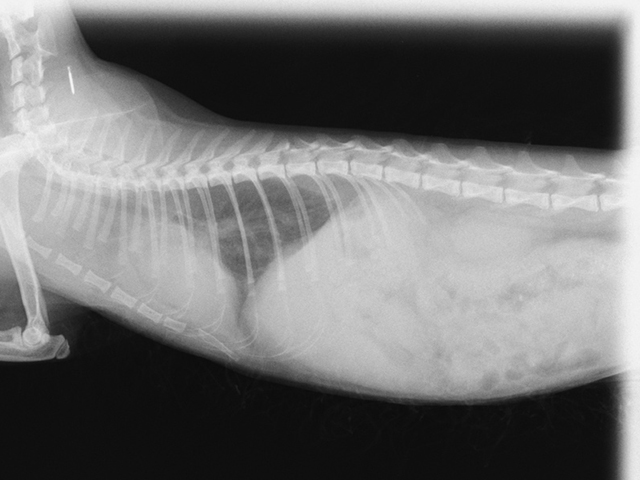

検査結果 蛋白分画、コロナウイルス抗体検査よりFIPを強く疑う。腹部及び胸部超音波検査にて腹腔内リンパ節の腫大と胸水貯留を確認。

診断 FIPウェットタイプ

治療 治験当日より注射薬の投与を開始。その後腹腔内リンパ節の腫脹、胸水消失し、状態安定。

初回来院時(2021.12.25)

食欲不振と元気消失があり、FIPを疑った飼い主さまが来院。